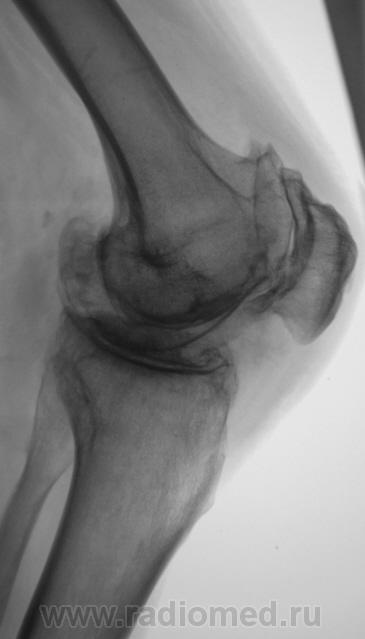

Боли в коленном суставе.

Деформирующий гонартроз 4 ст. или есть какой-то подвох? Двойной контур суставной поверхности медиального мыщелка бедра не Кениг ли случайно?

Мне показалось, что суставная щель вовсе и не так уж сужена.А вот в пателло-феморальный суставе резкое сужение суставной щели.Выраженный субхондральный склероз, краевые остеофиты суставных поверхностей костей.А что там у Косинской по этому поводу написано, помните?

Н.С. Косинская - уже в прошлом (с уважением)... Понятно, что здесь первоочередным критерием являются деформирующие (обезображивающие)

остеофиты, а не ширина суставной щели; и суставные концы костей уплощены ("просели" за счёт остеопороза), и м/мыщелковые бугорки сглажены (бывшие остеофиты).

А на Ваш взгляд "это" истинные остеофиты или окостенение мягкотканных компонентов?